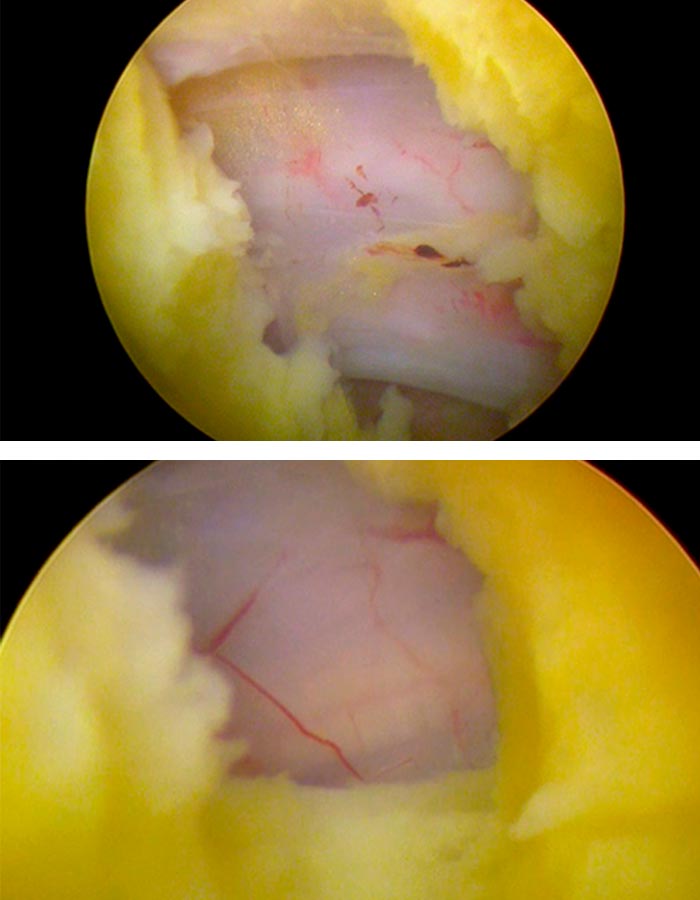

Tras localizar la zona de trabajo, suavizamos la hernia y procedemos a su retirada y al posterior sellado tanto del disco como del anillo donde ha salido la hernia para evitar futuras fugas.

Comprobamos adecuadamente que todas las estructuras neurológicas han quedado descomprimidas y liberadas y gozan de buen riego bascular.